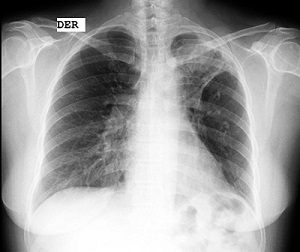

Se evalúa el caso teniendo en cuenta los valores de tiroglobulina, y ante la sospecha de un falso positivo se complementa el estudio con radiografía de tórax (fig. 4) y tomografía computada de tórax sin contraste (figs. 5 y 6), evidenciándose una lesión focal nodular en segmentos 1 y 2 del pulmón izquierdo de 42 mm de diámetro, con tractos fibrosos y bronquiectasias adyacentes. El primer planteo diagnóstico es de un aspergiloma, sin descartar proceso neoproliferativo primario.